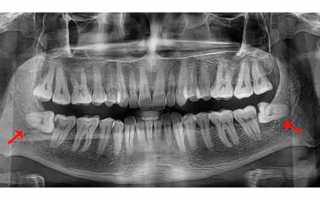

Зубы мудрости начинают формироваться у плода в утробе матери, и последними появляются в возрасте 17-25 лет. Удаление зуба мудрости на нижней челюсти может быть очень болезненным и становится трудным испытанием для многих людей.

Зубы мудрости получили свое название из-за возраста, в котором они появляются. К этому времени остальные 28 зубов уже находятся во рту. Поэтому зубам мудрости часто не хватает места и они остаются «застрявшими». Это явление называется ретенцией в стоматологии. Часто хирургам приходится удалять зуб мудрости на нижней челюсти, особенно у людей старше 30 лет, и это может иметь серьезные последствия.

- Зубы мудрости могут иметь разное количество корней — от одного до четырех. Определить точное количество корней часто бывает сложно.

Процесс удаления восьмого зуба на нижней челюсти изображен на фотографии выше.